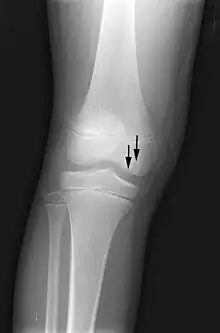

X-ray images of avascular necrosis in the early stages usually appear normal. In later stages it appears relatively more radio-opaque due to the nearby living bone becoming resorbed secondary to reactive hyperemia.[2] The necrotic bone itself does not show increased radiographic opacity, as dead bone cannot undergo bone resorption which is carried out by living osteoclasts.[2]

-

Radiography of total avascular necrosis of right humeral head. Woman of 81 years with diabetes of long evolution. -

Radiography of avascular necrosis of left femoral head. Man of 45 years with AIDS. -